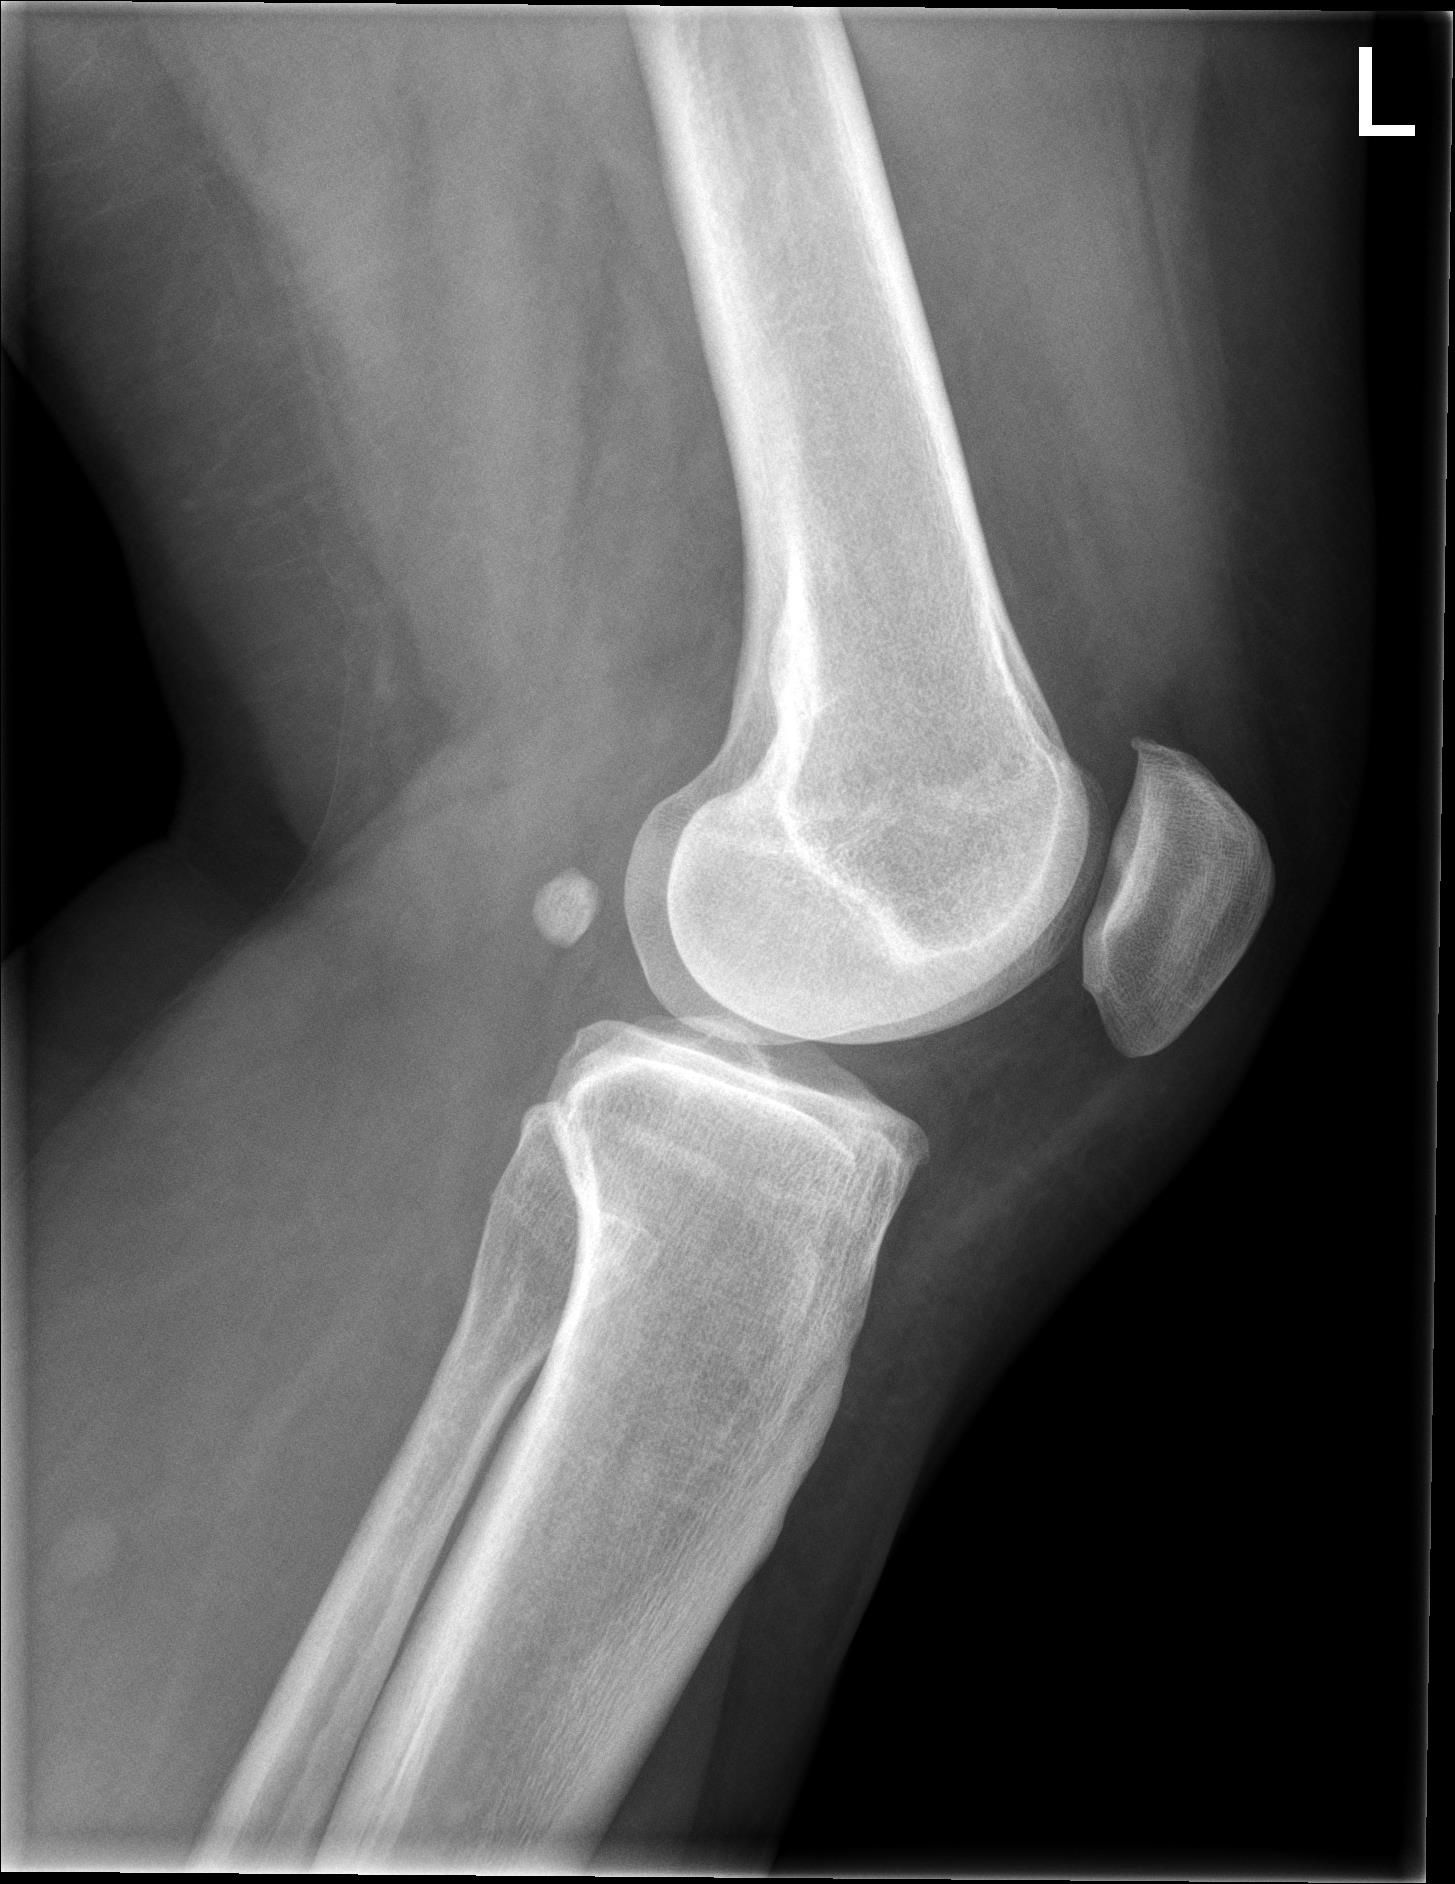

Patient A 53-year-old female patient presented at the emergency department with a locked left knee. The locking occurred whilst sitting in a chair in a flexed knee position. She was unable to unlock her knee due to the pain. On examination the knee was swollen and locked in a 70° flexion angle. An X-ray of the knee showed an inferior patellar dislocation without fractures (figure 1). Six years earlier she was treated with a medial open wedge HTO (OWHTO) with a proximal tuberosity osteotomy with a locked plate for valgus correction of medial compartment osteoarthritis. During surgery a planned 9° correction was performed. Insall-Salvati ratio (ISR) pre-operatively was 0.89. Directly after surgery ISR was 0.83 (figure 2, figure 3). Her postoperative course was uneventful, and the final results were excellent until her recent presentation.

Intervention After administrating analgesics, a reduction was performed by hyperflexing the knee, unlocking the superior patellar osteophyte from the trochlear groove (figure 4.) After two weeks of weight bearing in an extension splint, the patient was advised to resume normal activities. After reduction of the patellar dislocation the X-ray showed an ISR of 0.74. The X-ray also showed a suprapatellar osteophyte.